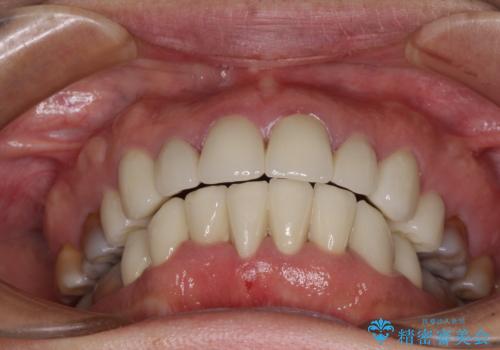

数十年に及んだ歯の変色が改善されたため、大変満足していただきました。

気になる変色歯を仮歯に変え、その後歯列不正を矯正治療で改善し、最後にオールセラミッククラウンにて補綴治療することとしました。